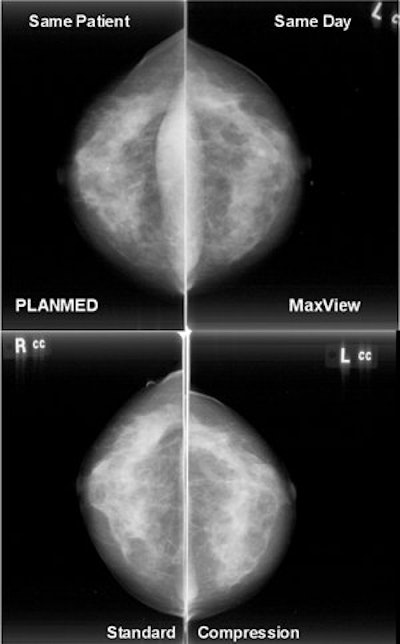

![]() |

| Images obtained with and without the MaxView Breast Positioning System, which uses biphasic compression. Image courtesy of PlanMed. |